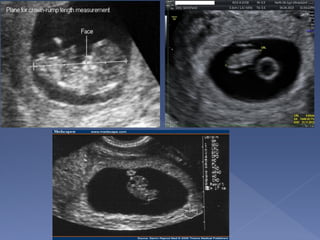

 Measure from top of head

to rump

 Always measure in neutral

position

 made between 7 to 13

weeks

 Very accurate(Dating

with the CRL can be

within 3-4 days of LMP)

 it should not be changed

by a subsequent scan.